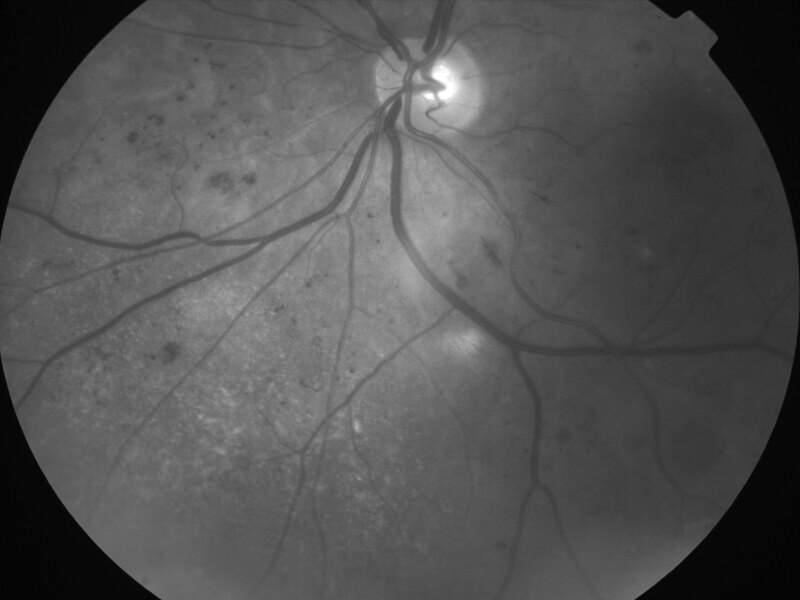

rétinopathie diabétique pré-proliférante

IM000004.jpg